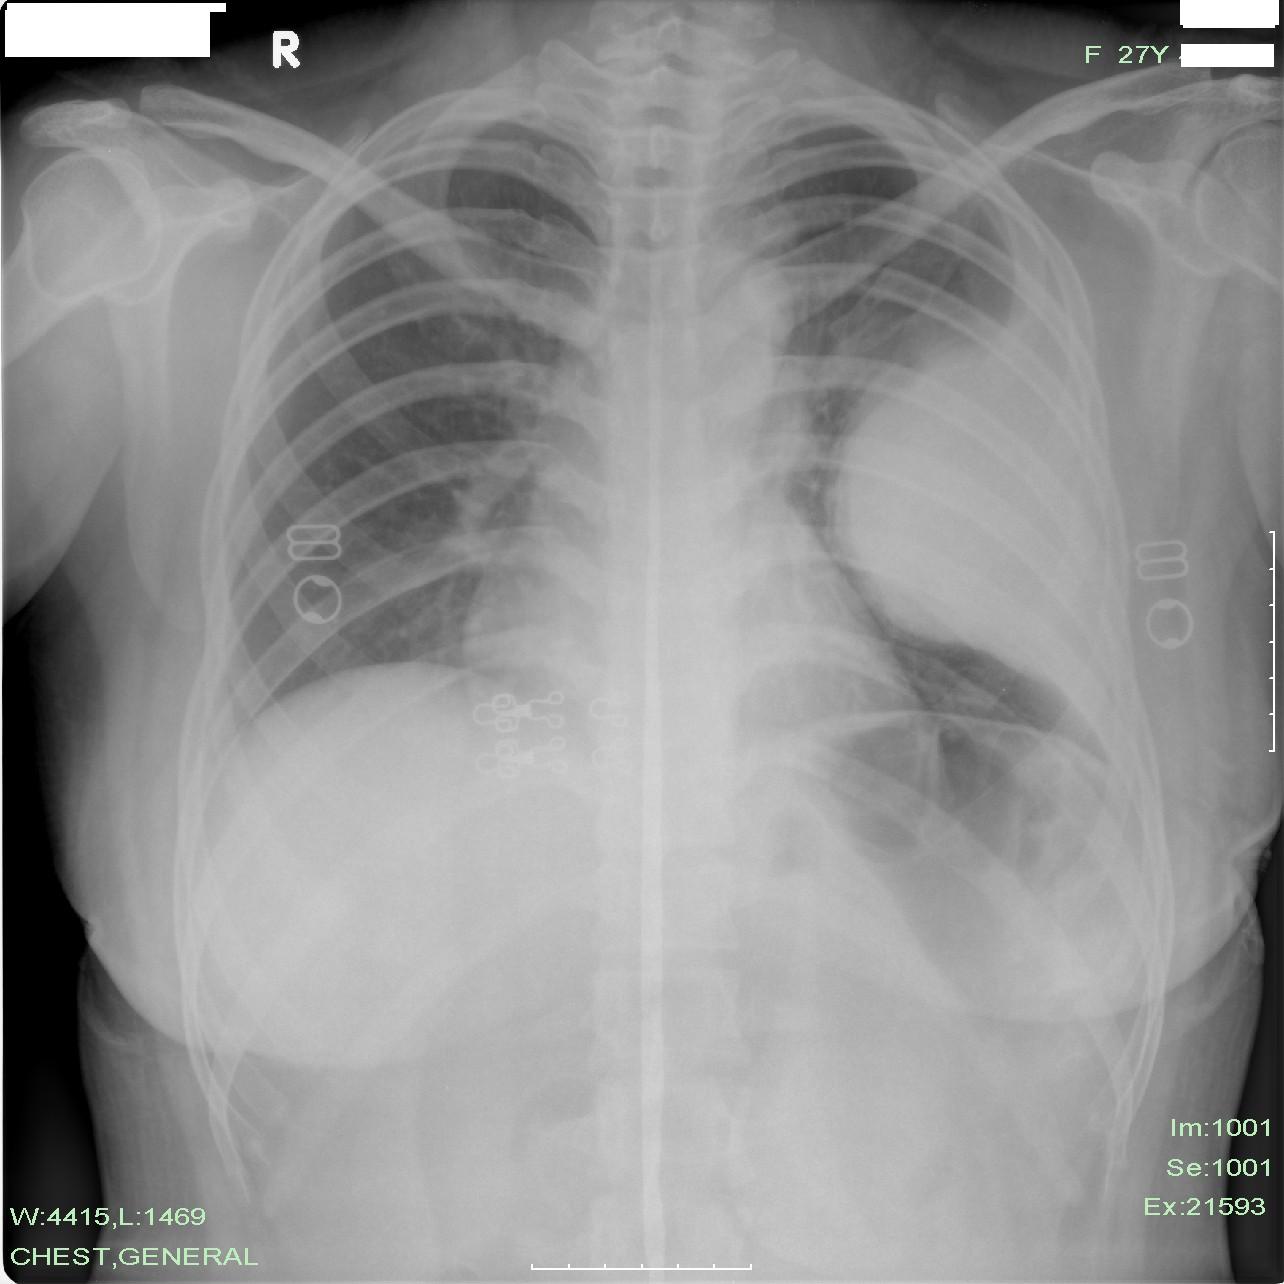

以下是引用wangdch2008在2008-4-21 11:09:00的发言:[br]左侧包 裹性胸腔积液可能性大

以下是引用chenwei198421st在2008-4-21 11:42:00的发言:[br]病理是来源于肺的小细胞性神经内分泌癌!谢谢大家支持!

以下是引用宇宙ct在2008-4-21 10:58:00的发言:[br]间皮瘤?